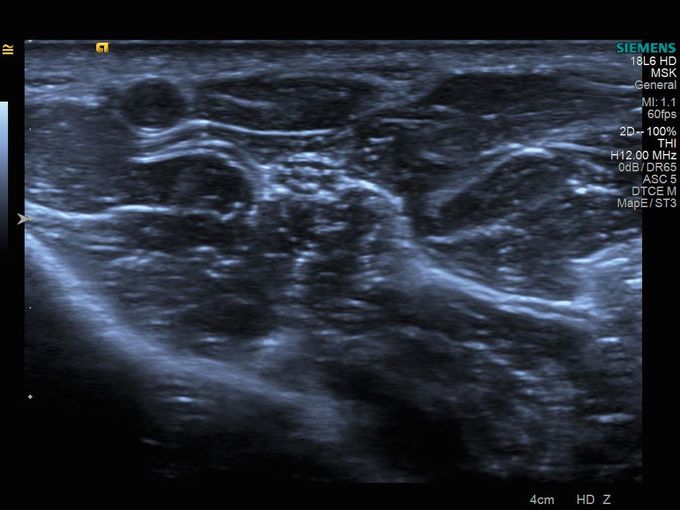

Кроме новой техники, можно заказать восстановленные медицинские системы: ультразвуковые сканеры, томографы, флюороскопы, ангиографы и хирургические установки С-дуга.